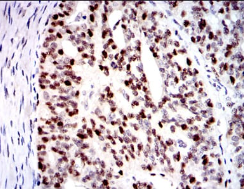

IHC    1/200 - 1/1000